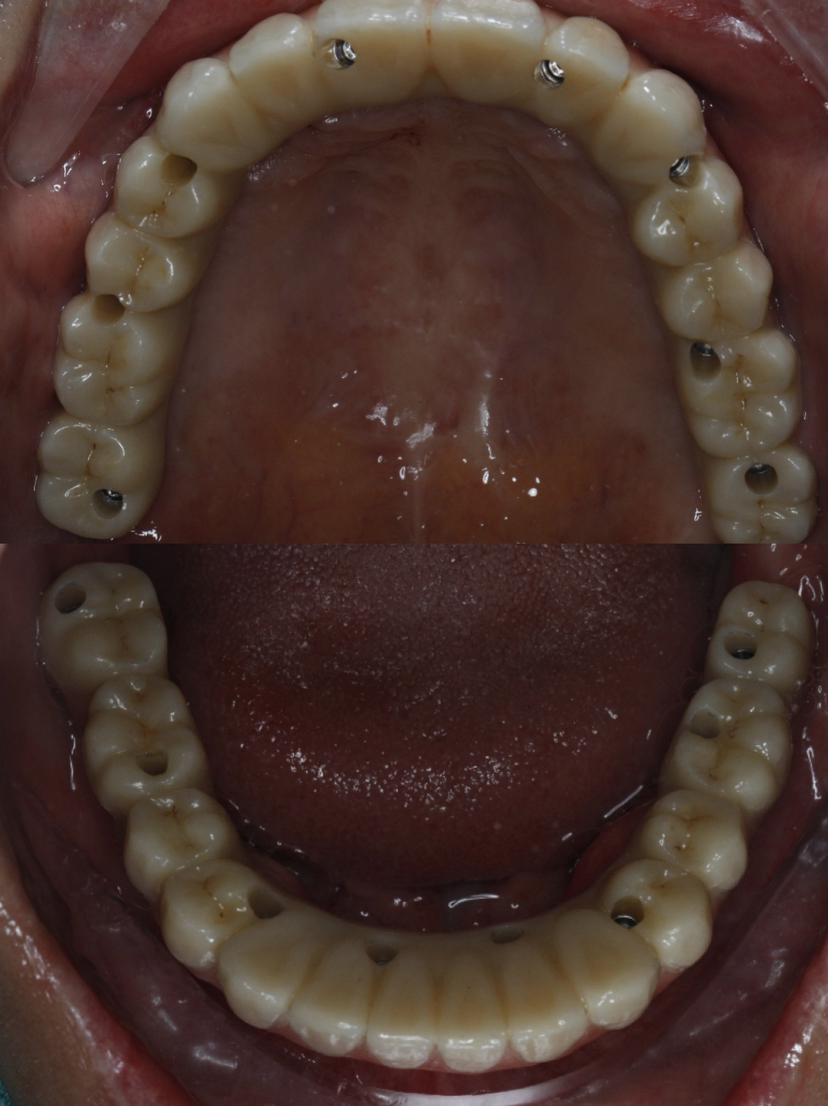

该患者就是因牙周病导致牙齿松动脱落,我们通过在全口牙槽骨上植入16颗种植体,然后在种植体上安装连桥牙冠,从而恢复半口牙齿的咀嚼功能和美观。相对于传统的种植修复方式缺一颗种一颗。4-8颗种植体的种植手术创伤相对较小,大大的减少了患者的疼痛感。